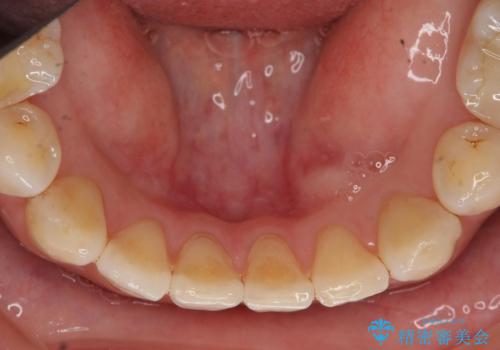

CTでみたところ、下の犬歯が内側に倒れこんでおり、根の先が顎の骨から出かかっている状態でした。おそらくその影響で犬歯の神経が失活してしまったのであろうと思われます。(フェネストレーションといいます)

検査した結果下の両側の犬歯の神経が失活しており、根の治療が必要な状態でした。

一見歯がきれいに並んでいても、中の根の先の位置までしっかり矯正治療で丁寧に動かさないと、今回のように神経が失活するリスクがあるので、注意が必要です。